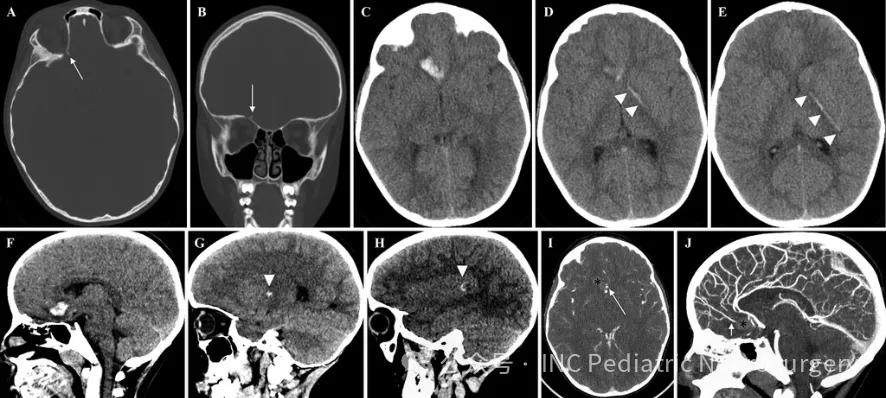

影像学检查显示,杰克的右侧额叶存在脑实质出血,并向左顶叶延伸,经过胼胝体膝部、左侧苍白球、内囊前肢和左侧后部岛叶,同时伴有右侧眶顶骨折和局灶性蛛网膜下腔出血。

然而,血管造影却显示,尽管铁杆已穿入颅脑,但颈内动脉、基底动脉和椎动脉的颅内分支通畅,无明显狭窄或颅内夹层迹象。这也表示,尽管尖端从右侧眼眶上方穿过眼球顶部,刺入颅内,且穿过骨性眶顶,但却十分“巧合”地避开了大脑前动脉,勉强避开了内囊后肢,最终停在对侧的左侧颞上回。

此外,眼科检查也未发现视力受损,但有轻微的结膜下出血。